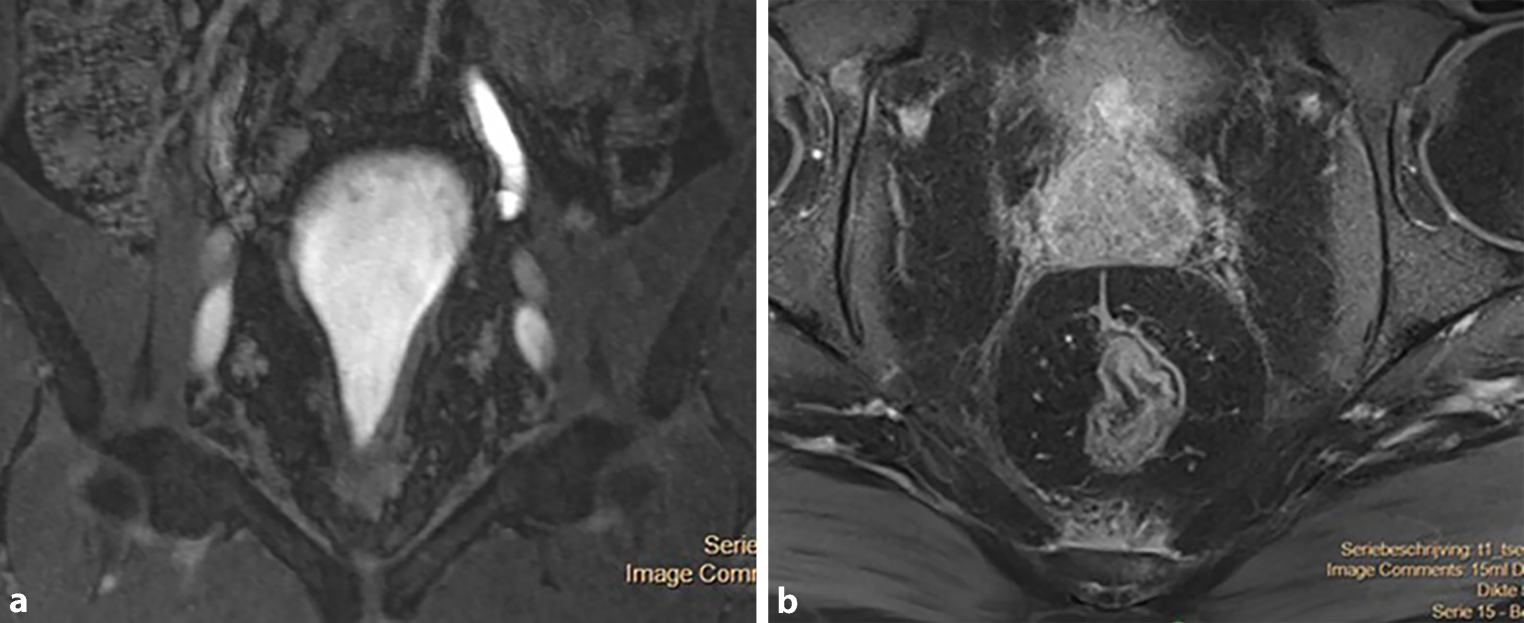

Macroscopisch presenteert cystitis cystica zich als submucosale translucente noduli. Het onderscheid met bijvoorbeeld cystitis follicularis is goed te maken, omdat de noduli bij cystitis follicularis een meer solide en grijzig aspect hebben. Bij cystitis glandularis hebben de noduli juist een meer villeus en langwerpig aspect (zie fig. 1a en 1b) of is er een poliepachtig beeld (zie fig. 1c). In histologisch opzicht wordt bij cystitis glandularis onderscheid gemaakt in het klassieke type en het intestinale type. Bij het intestinale type is sprake van intestinale metaplasie, gekenmerkt door zegelringcellen, die normaal gesproken alleen voorkomen in colonepitheel [3].

Figuur 1

a Urethra prostatica van patiënt met cystitis glandularis en pelvic lipomatosis. b Urethra prostatica van patiënt met cystitis glandularis en pelvic lipomatosis. c Cystitis glandularis in de blaas

Bij cystoscopie wordt een eerste inschatting gemaakt van de macroscopische kenmerken. Cystitis glandularis komt het meest uitgesproken ter hoogte van het trigonum voor of in de urethra prostatica (zie fig. 1a en 1b), maar kan ook verspreid in blaas zichtbaar zijn (zie fig. 1c). Bij uitgebreide afwijkingen in de blaas dient de nierfunctie te worden bepaald en moet beeldvorming van de hoge urinewegen worden verricht. Als de nierfunctie het toelaat, kan een CT-scan met uitscheidingsfase een beeld geven van zowel de mate als de oorzaak van de hydronefrose, als van de anatomische verhoudingen en eventuele mate van pelvic lipomatosis. Bij dit laatste wordt een peervormige blaas gezien (zie fig. 2a), met uitgesproken perirectale en perivesicale vetstructuren (zie fig. 2b). Deze vetstructuren kunnen ook leiden tot bilaterale hydronefrose en gemedialiseerde ligging van de distale ureteren. Afhankelijk van mate van hydronefrose en eventuele behandelconsequenties, kan de diagnostiek worden uitgebreid met een renogram.